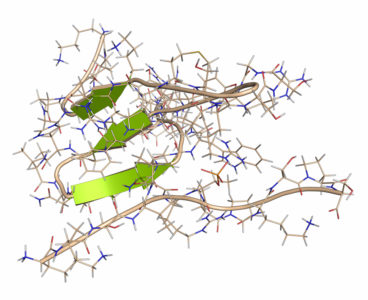

Taking a pill that prevents the accumulation of toxic molecules in the brain might someday help prevent or delay Alzheimer’s disease, according to scientists at Baylor College of Medicine, Texas Children’s Hospital and Johns Hopkins University School of Medicine. The study, published today in Cell Press journal Neuron, took a three-pronged approach to help subdue early…

Taking a pill that prevents the accumulation of toxic molecules in the brain might someday help prevent or delay Alzheimer’s disease, according to scientists at Baylor College of Medicine, Texas Children’s Hospital and Johns Hopkins University School of Medicine. The study, published today in Cell Press journal Neuron, took a three-pronged approach to help subdue early…